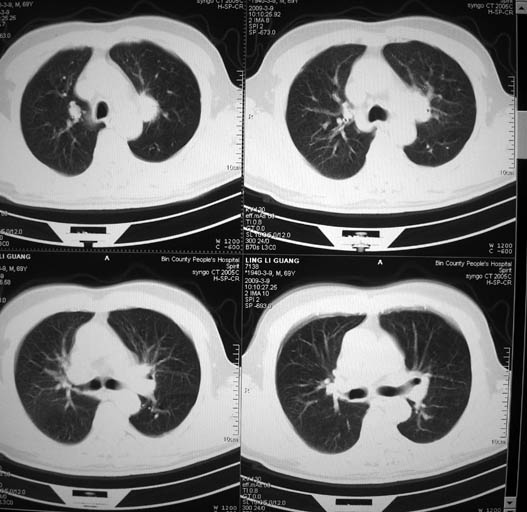

以下是引用随光逐影在2009-3-9 21:36:00的发言:[br]1)两肺上叶尖段结节状病灶,性质待定(不排除肿瘤可能);建议追踪复查。2)右肺中叶内侧段炎症。